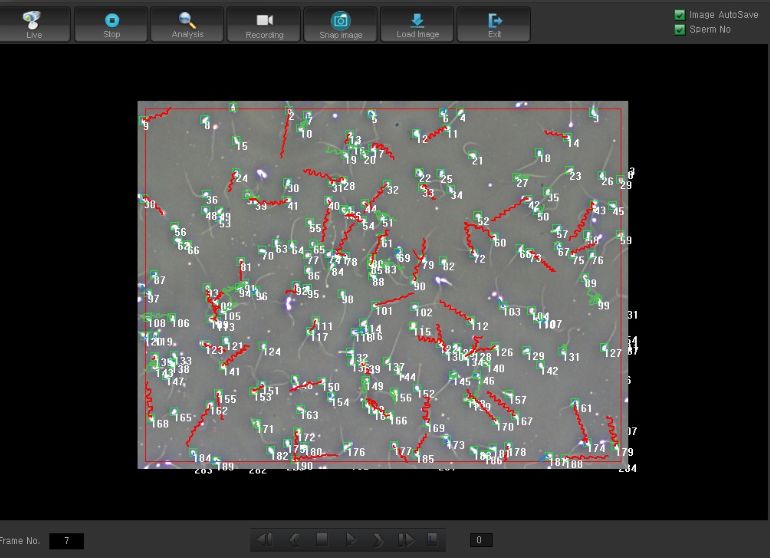

2013년 미국불임학회(ASRM) P-1040

시험관 시술에서 임신 예측을 위하여 운동성 있는 총 정자 숫자의 효용성

2013년 미국불임학회(ASRM) P-1040

시험관 시술에서 임신 예측을 위하여 운동성 있는 총 정자 숫자의 효용성